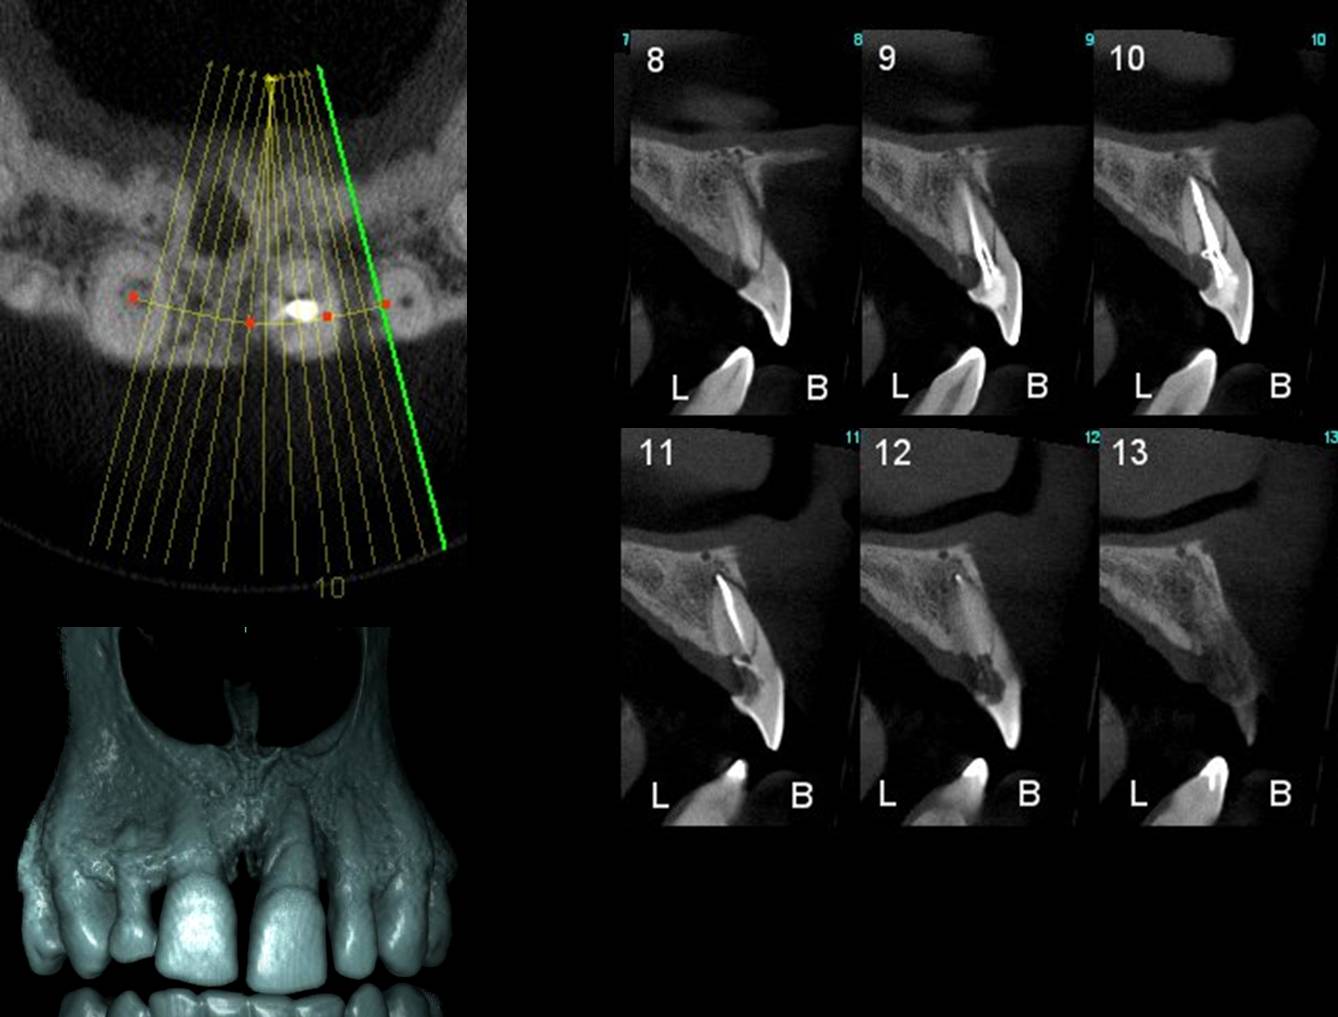

سی تی اسکن دندانپزشکی

CBCT تکنولوژی جدیدی است که قدرت تشخیصی بسیار بالایی دارد. قدرت افتراقی بالای این روش به دندانپزشک اطلاعات پردامنه در مورد موضع درمان قبل از شروع درمان میدهد. در تشخیص ضایعات، تشخیص برخی از شکستگیهای ریشه و در طرح درمان جراحیهای ریشه کاربرد دارد و هر روز اندیکاسیونهای جدیدی برای این تکنیک معرفی میشود.